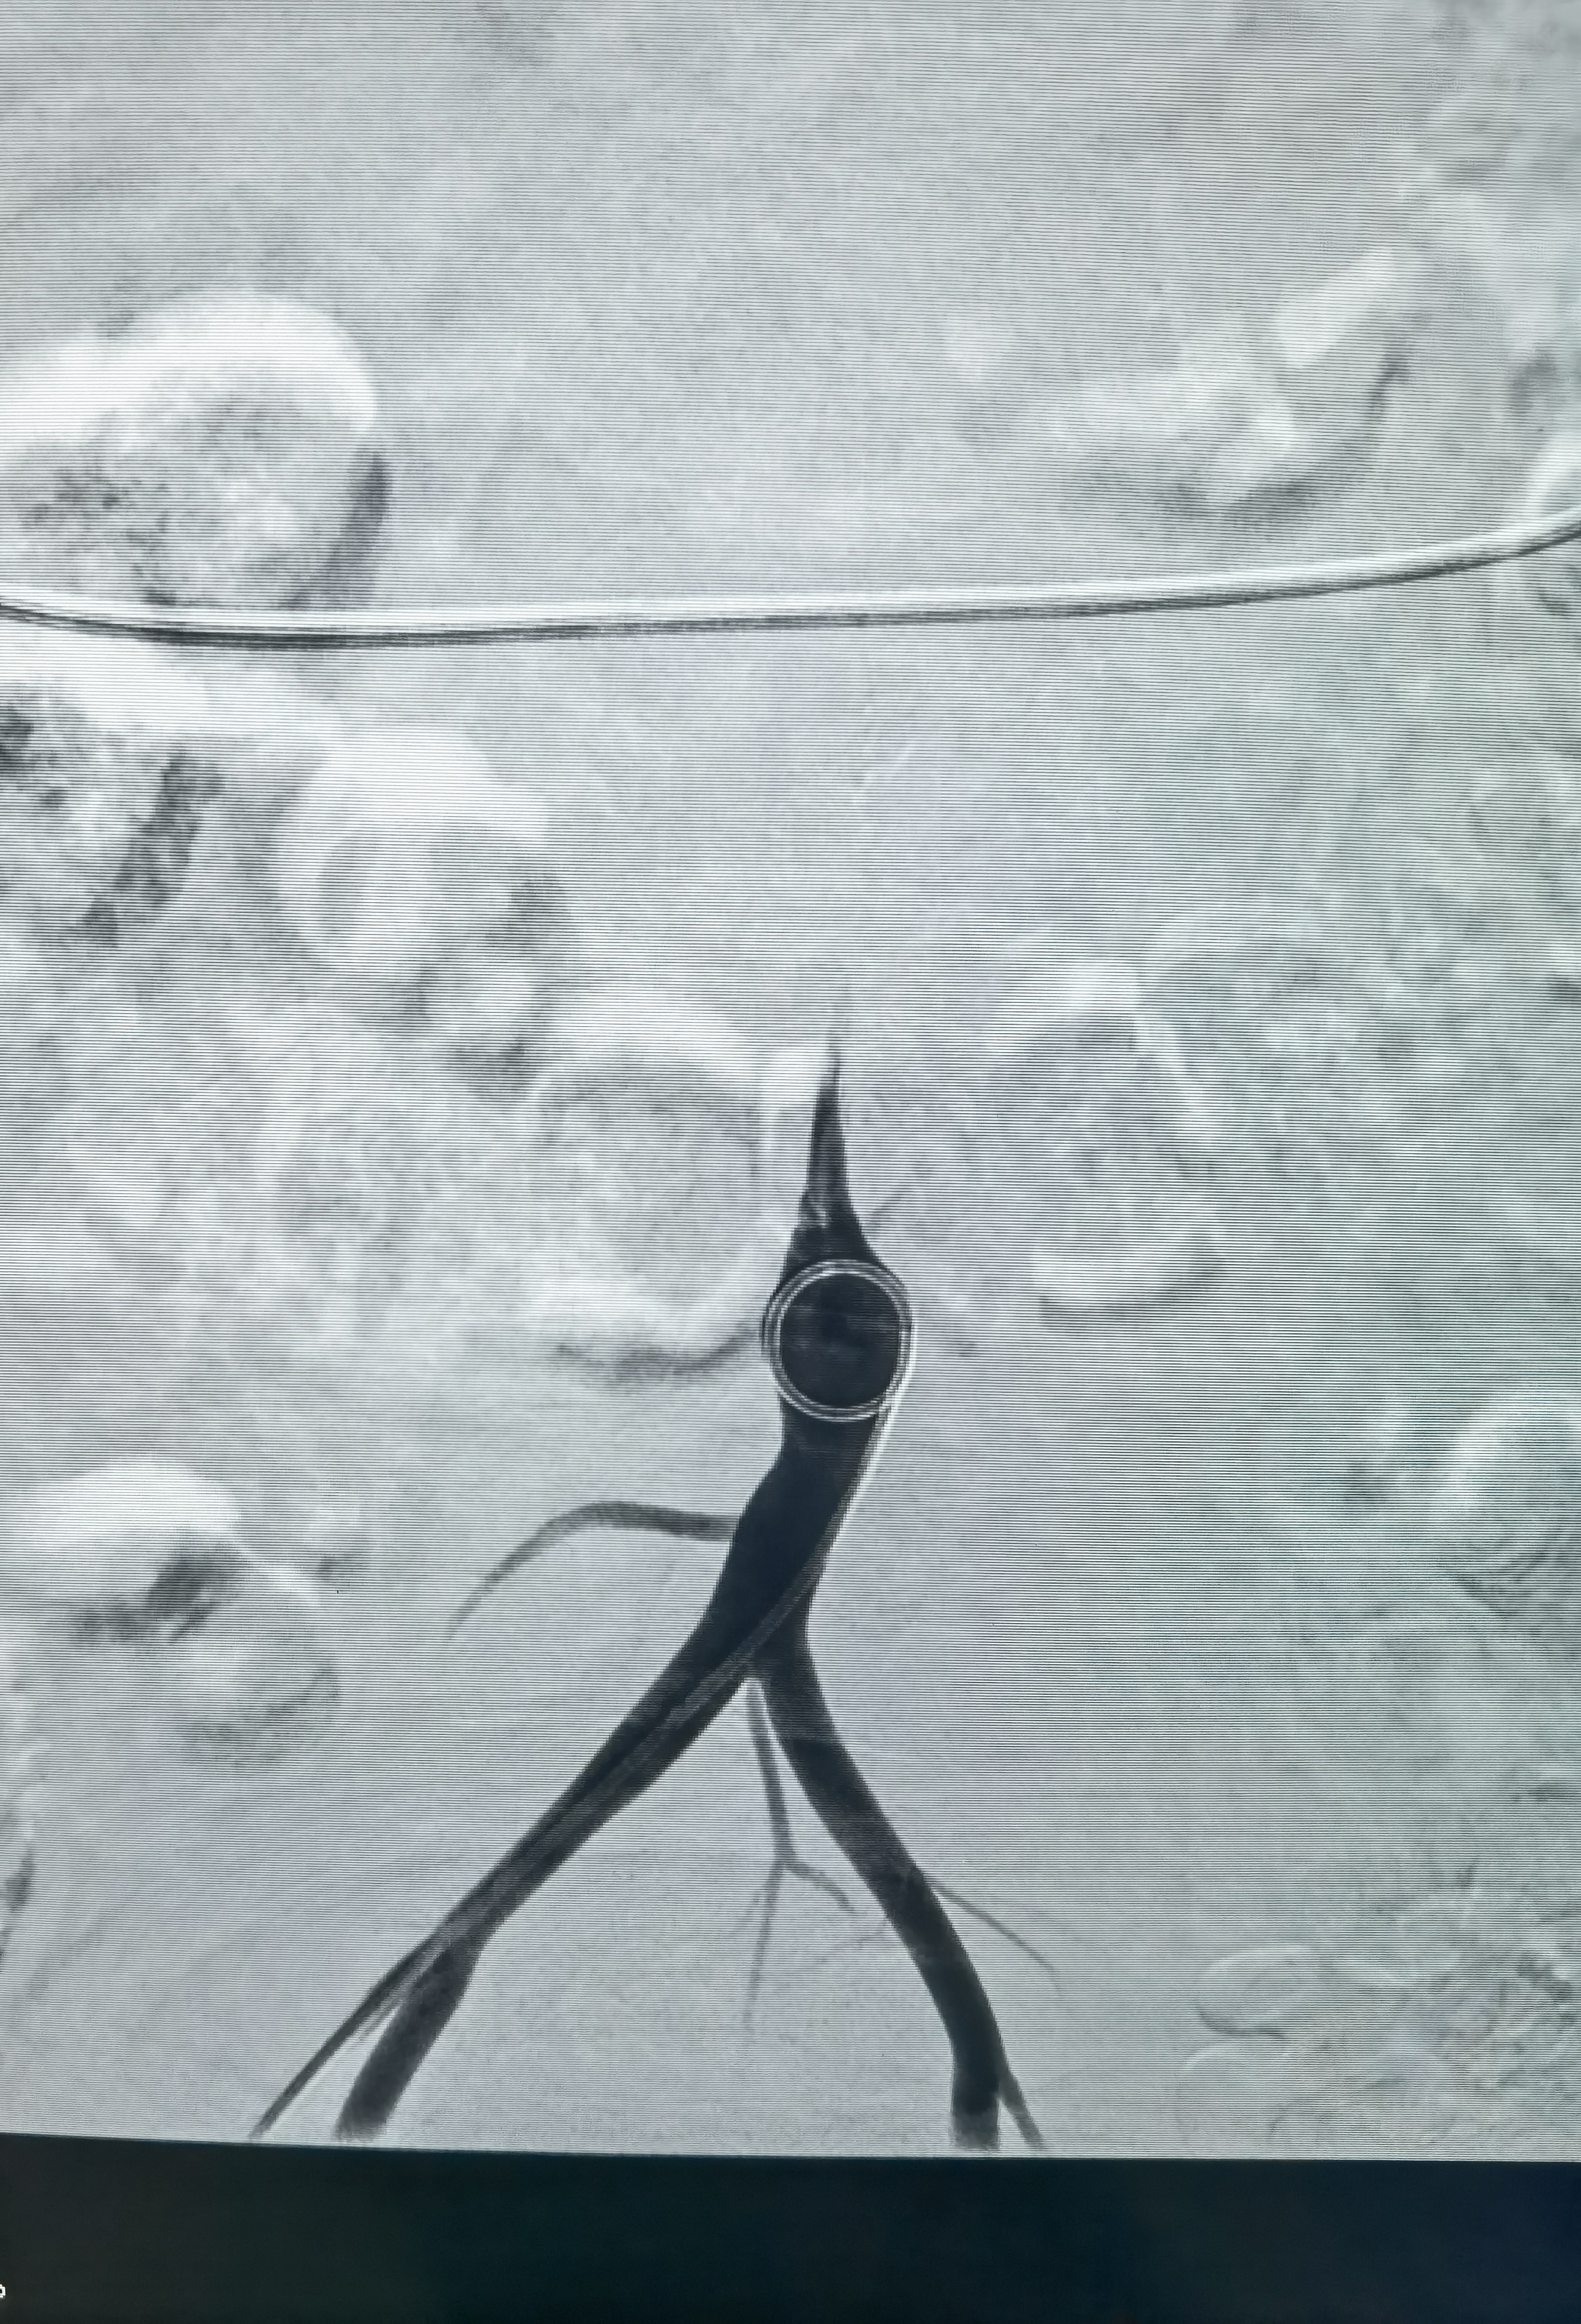

再上取栓支架,这是取栓支架打开造影,能看见支架压缩影,提示有狭窄!

支架取栓两次没通,不敢过多用支架拉了,上球囊扩张两次,大脑中水平段扩一次,远端扩一次!

扩完血流恢复,血管通了,但是大脑中动脉M1仍有血栓,似乎还有点夹层,动脉给了10ml替罗非斑,观十余分钟,M1血栓又增加了,血流也变差,怎么办?想支架成型,但是患者有大动脉炎,不贴支架血流维持不住,术中商量一下考虑患者年轻,还是要尽量让患者降低瘫痪的机率,遂决定植入药物涂层支架,就算动脉炎引起支架内闭塞也需要一定时间,患者大脑前有通过软膜支向大脑中供血区代偿,到时候慢性闭塞可能患者不会出现严重影响!

药物涂层支架

支架植入后血流完成恢复!